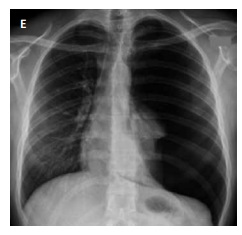

Assinale a alternativa que corresponda ao exame de imagem compatível ao caso clínico apresentado.